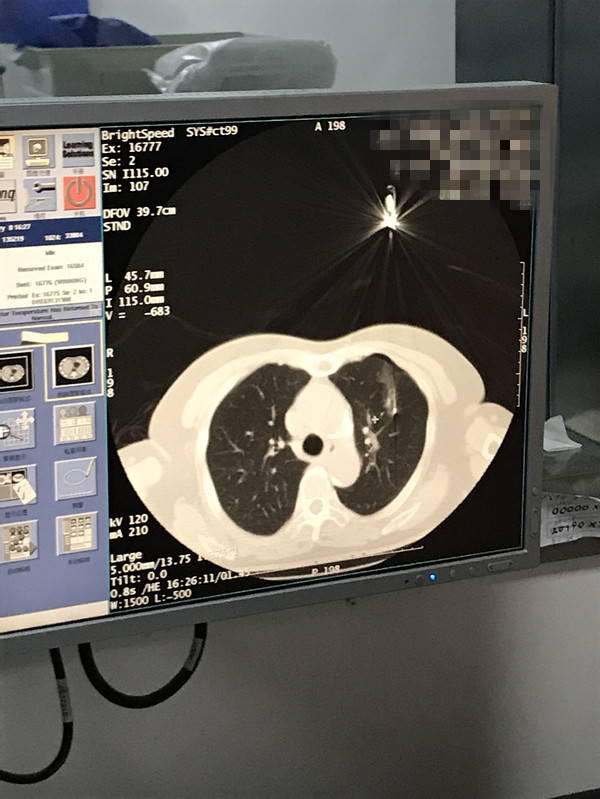

下一篇:2021年1月份肺部氩氦刀手术